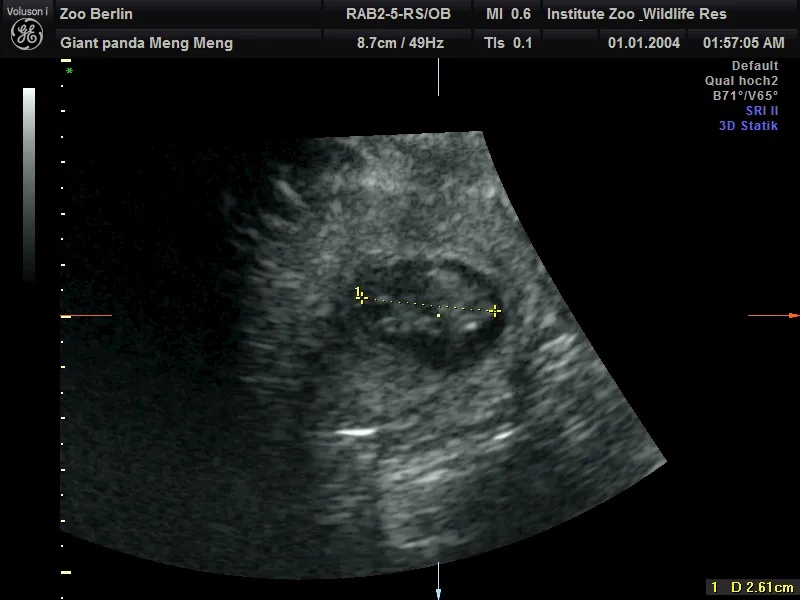

在园方11日上午进行的超声检查中,工作人员清楚地检测到两个熊猫胎儿的心跳。目前两个胎儿身长约2.5厘米。

柏林动物园介绍,根据目前胚胎的大小,如果一切顺利的话,大熊猫双胞胎预计将于8月底出生。